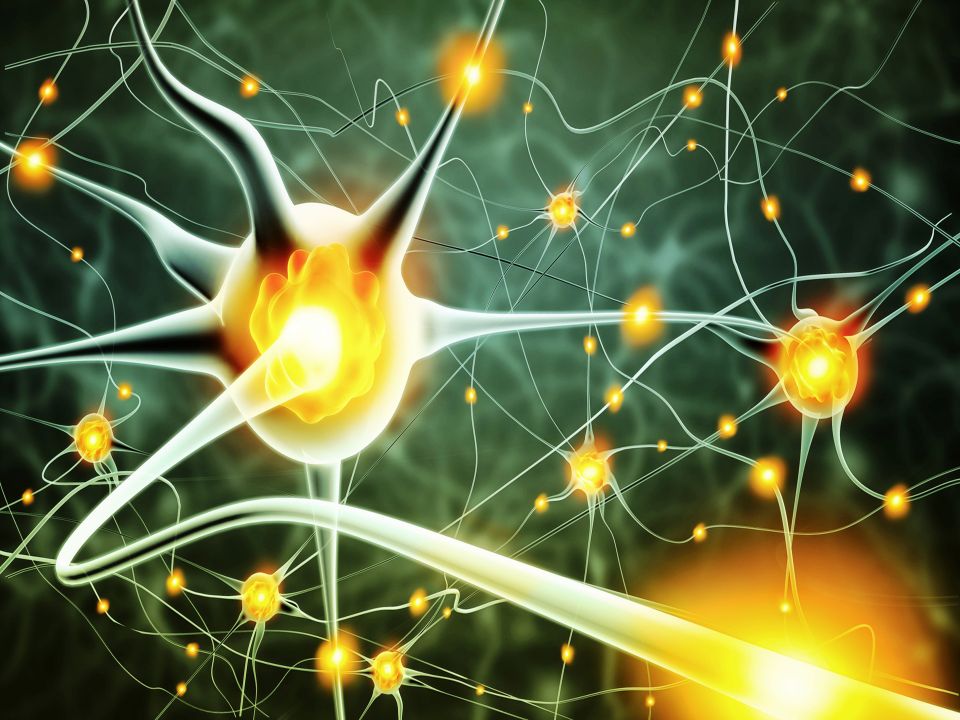

Skin receptors report a painful stimulus by sending electrical messages along sensory nerve fibers to the spinal cord. From there they travel to the brain, where the signals are interpreted as the sensation of pain. Sometimes you can feel pain in one part of the body even though the area affected is actually elsewhere. This is called referred pain, and one example is angina pain originating from oxygen starvation of the heart muscle but felt in the upper arm, shoulder and neck.

At times of acute stress, the brain produces chemicals called endorphins. These reduce the perception of pain by blocking the action of the chemical messengers that transmit pain signals between nerve cells.

Pain may be partly or completely blocked by a process known as ‘gate control’. Nerve messages carrying information from the skin about other sensations can sometimes bar the transmission of pain messages. This happens when nerve fibers that are carrying ‘non pain’ messages prevent nerve fibers that are carrying pain messages from relaying these signals up the spinal cord. It explains why therapies involving touch, pressure, heat and cold can relieve pain.